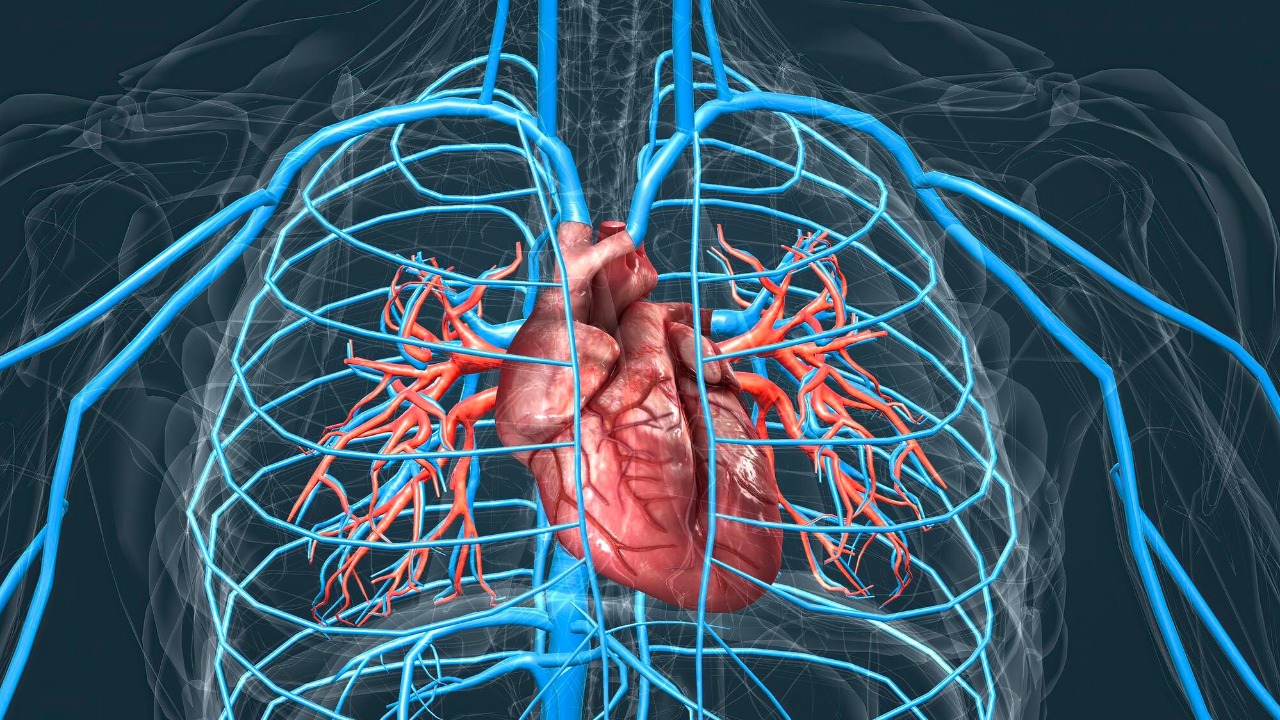

Scientists uncover stunning proof your heart can repair itself

Read More: Scientists uncover stunning proof your heart can repair itselfFor decades, cardiology textbooks treated heart damage as permanent, a grim one-way street from heart attack to heart failure. A…